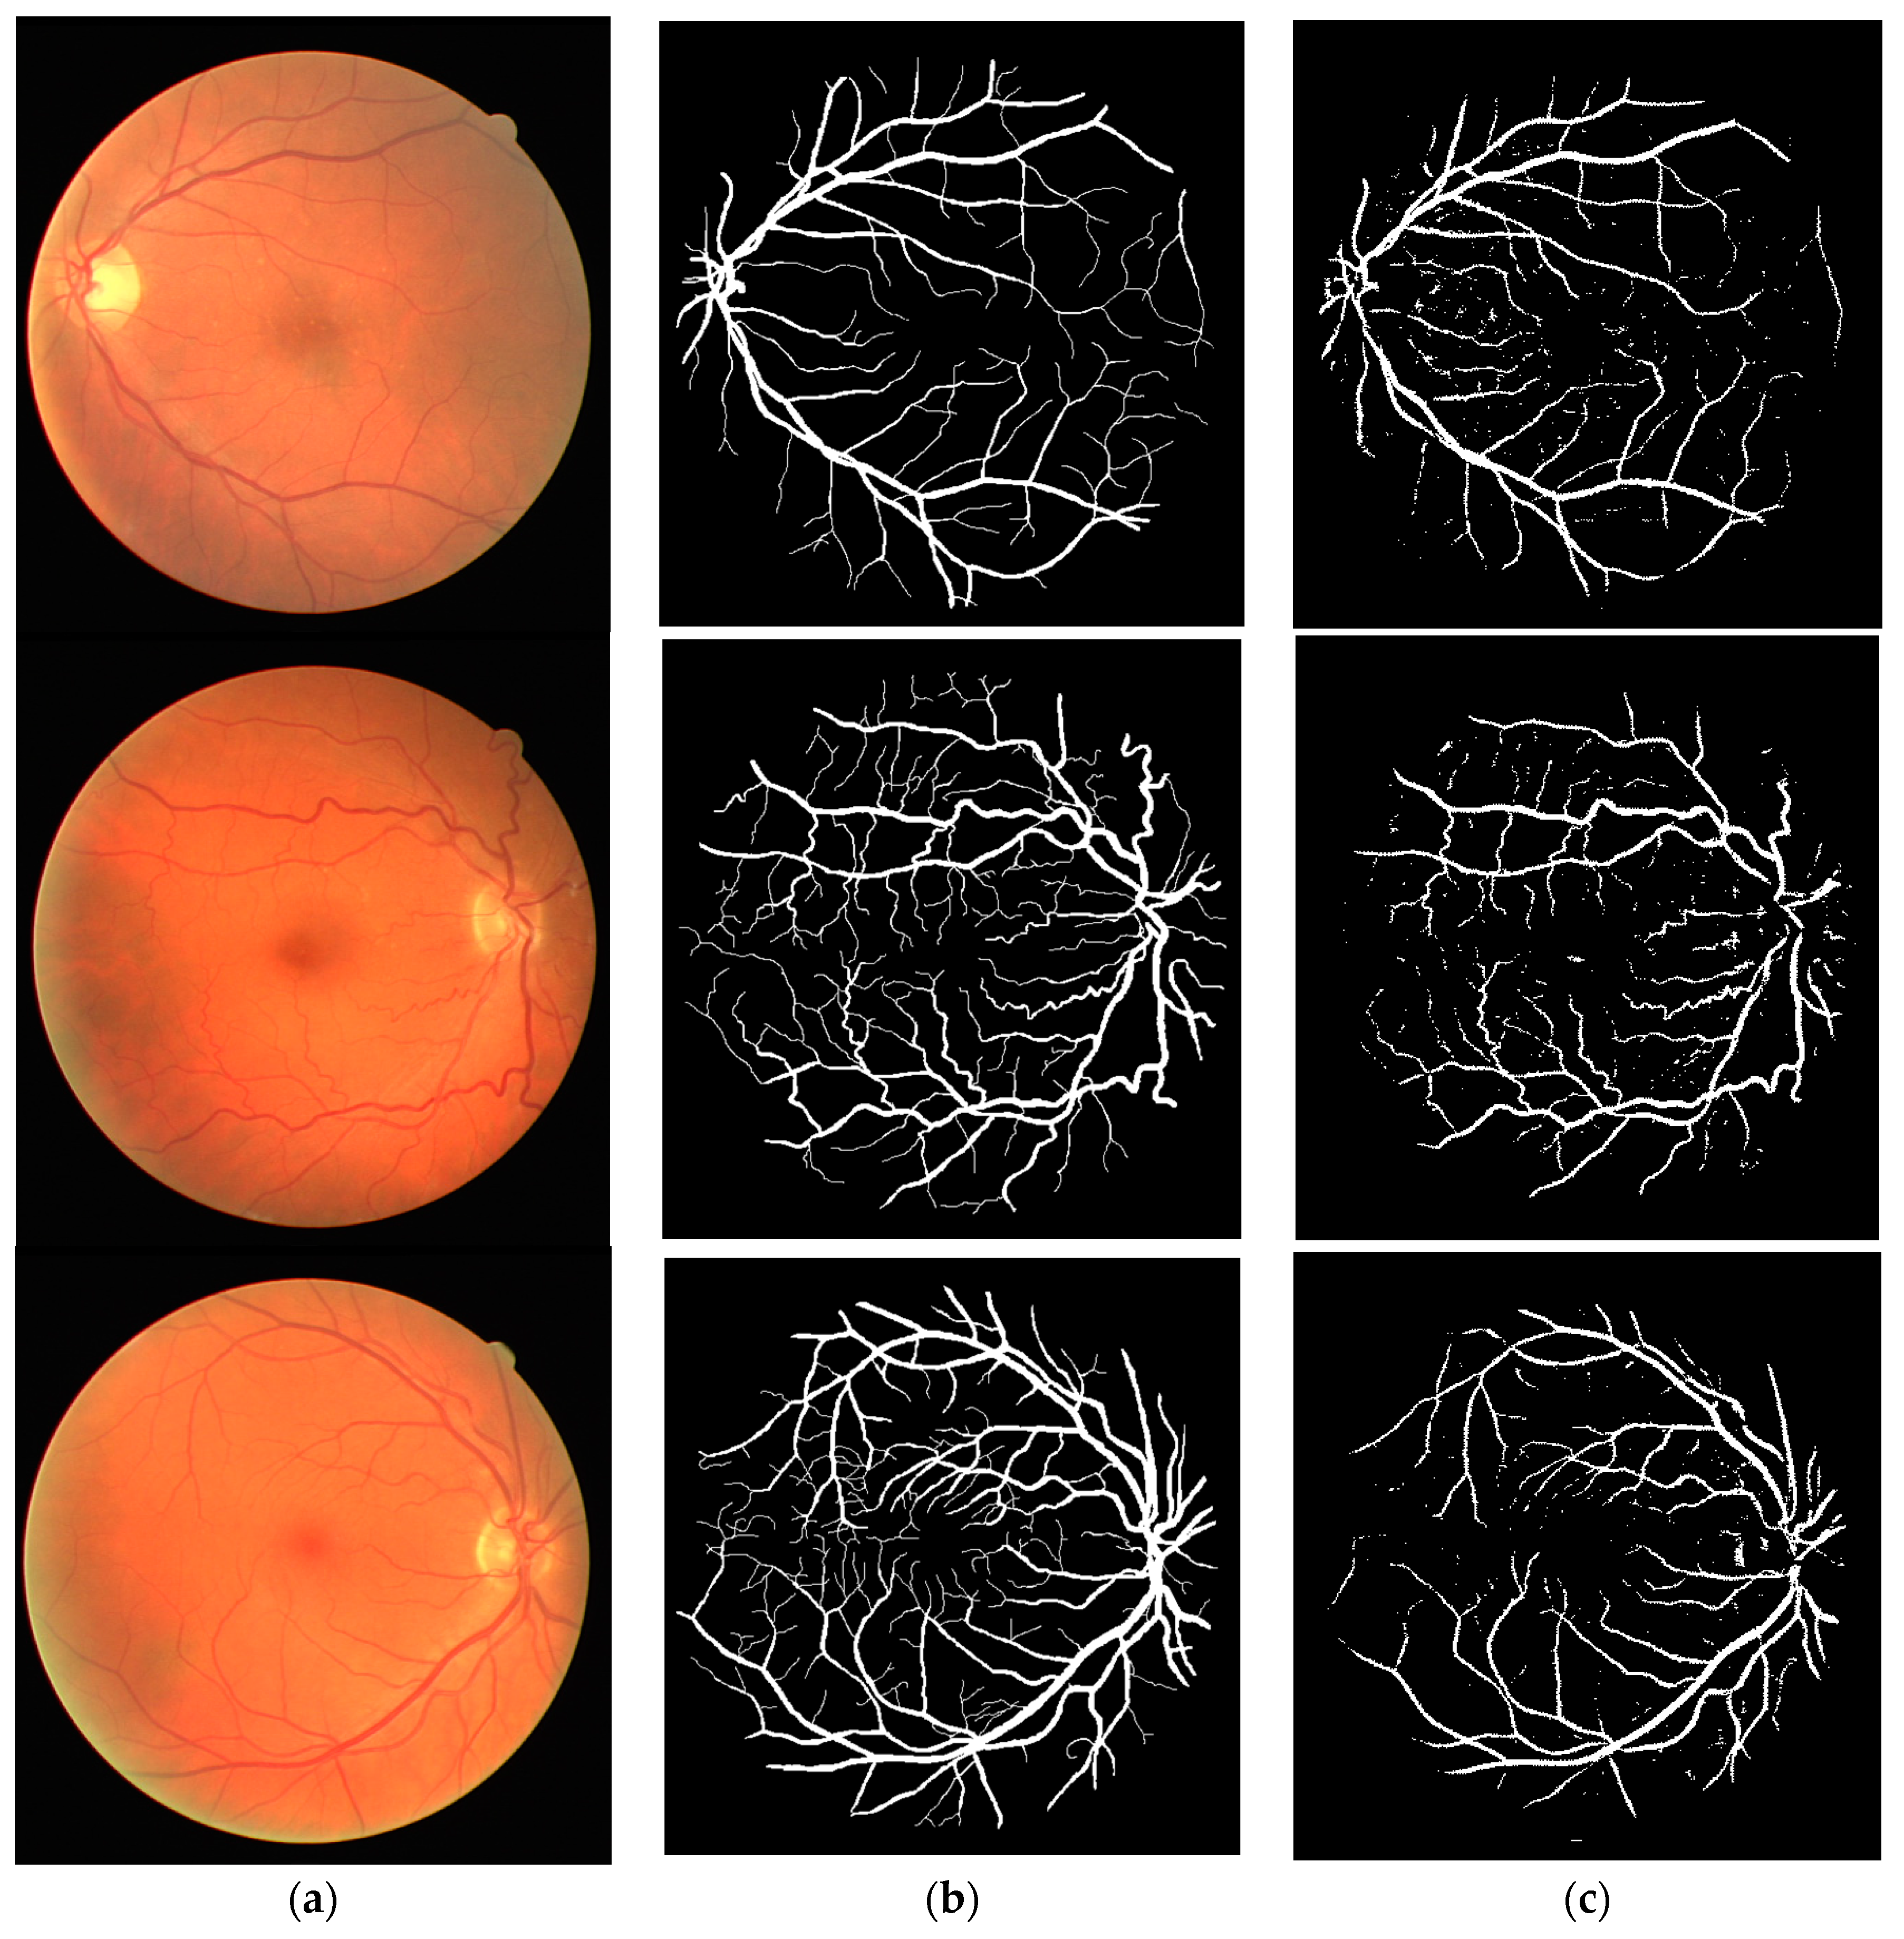

3.2. Experiment on Retinal Vessel Detection